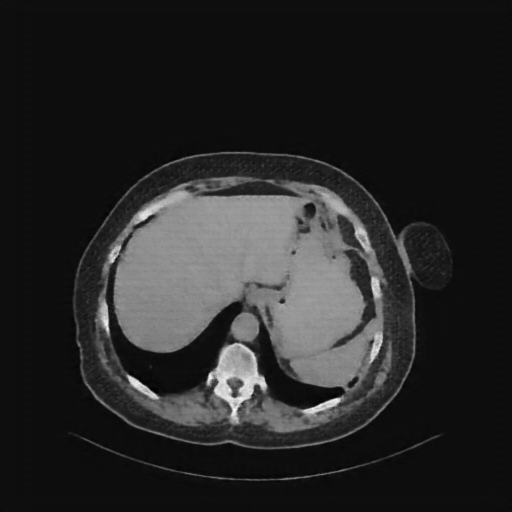

Generated VENOUS CT scan (AβB translation)

Full window (WL 1023.5, WW 4095 β Low β1024, High +3071)

Actual HU range: [-855.0, 775.1]